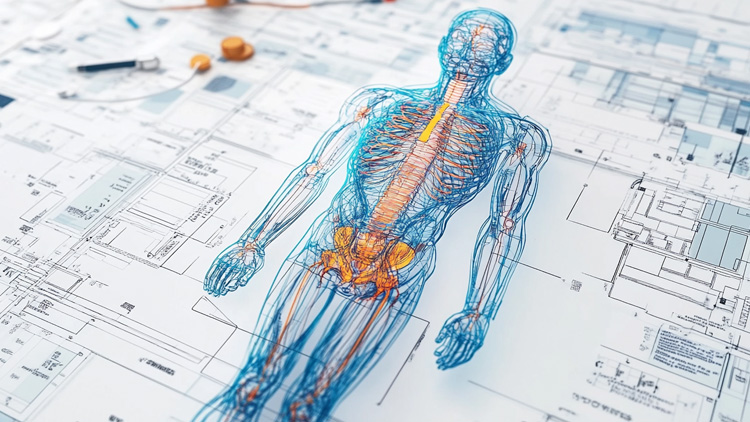

Discover how CollectiveX's AI-powered platform is enhancing diagnostic accuracy and treatment planning. By combining global medical expertise with advanced artificial intelligence, we're improving patient outcomes and revolutionizing healthcare delivery.